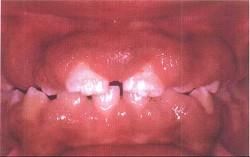

问题 药物性牙龈增生的临床表现是()

选项 A.龈乳头可呈球状、结节状 B.上下前牙区较重,一般不易出血 C.只发生于有牙区 D.最根本的治疗是停药或换药 E.以上全是

答案 E